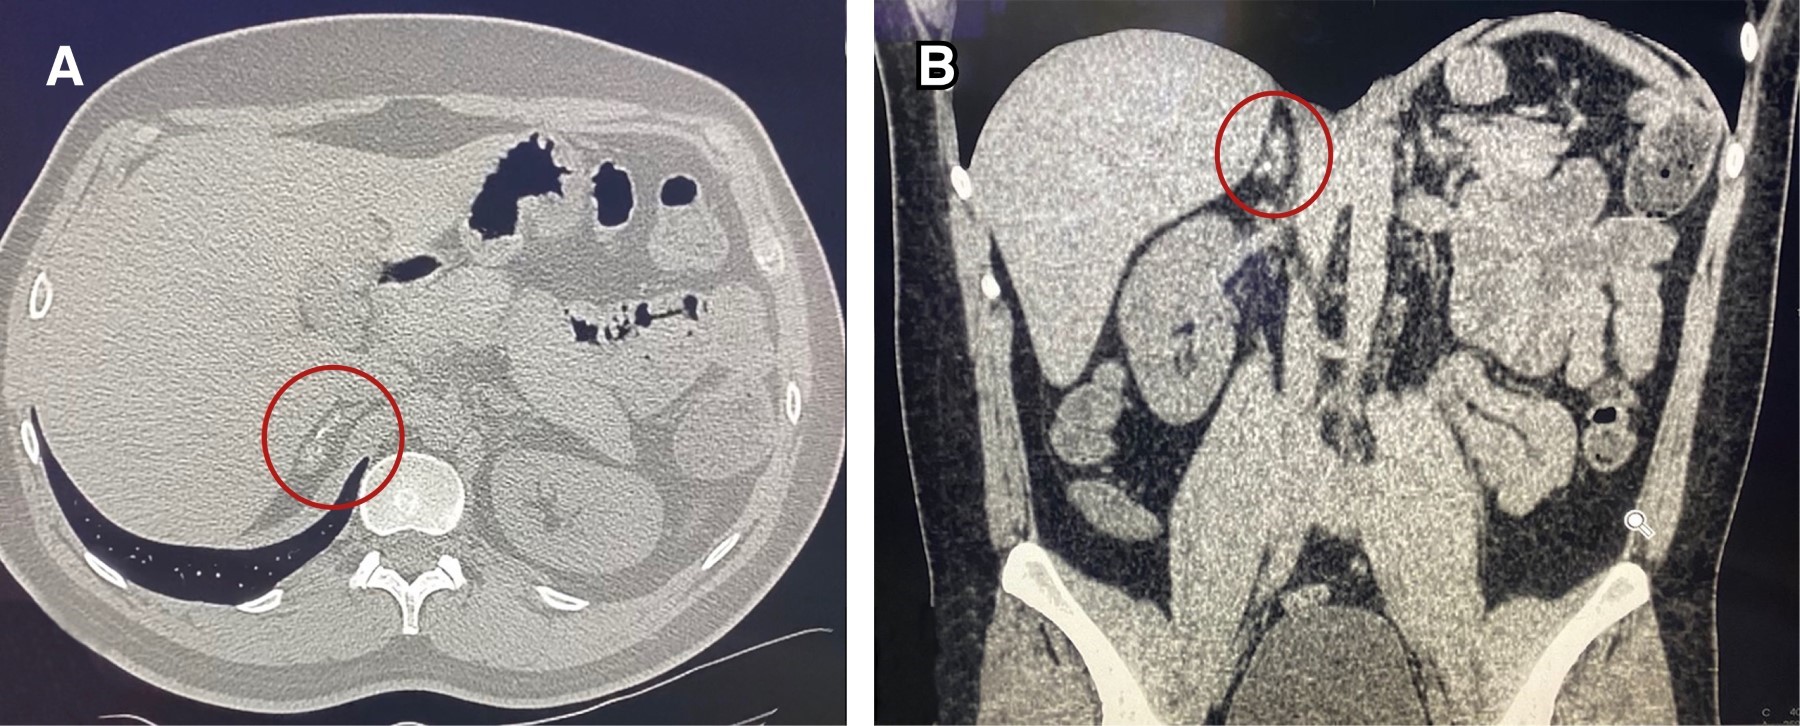

Se realizaron tres adrenalectomías laparoscópicas transperitoneales, en el periodo de 2016 a 2021. La edad media de presentación fue de 48 años, dos del sexo masculino y uno del femenino. El estudio en donde se realizó el hallazgo de incidentaloma fue la tomografía en los tres pacientes. En la mujer, el motivo fue una revisión de rutina (check-up). En los hombres, uno fue por protocolo preoperatorio de hernia de pared abdominal y el otro por dolor abdominal por apendicitis (Figura 1). A los tres pacientes se les efectuaron valoraciones hormonales, en dos de ellos resultaron normales, por lo que se les hizo la prueba de supresión de dexametasona reportándose en parámetros normales (Tabla 1). Ninguno tenía antecedentes oncológicos.

Las cirugías se llevaron a cabo sin incidentes ni complicaciones (Figura 2). La media del tamaño del tumor fue de 3 cm. El promedio de tiempo quirúrgico fue de 90 minutos, 40 mL de sangrado transoperatorio y dos días de estancia hospitalaria (Tabla 1).

El primer estudio de imagen en donde se detectó el incidentaloma fue la tomografía abdominal en todos los pacientes. Durante su evaluación inicial, en la revisión de las tomografías se observó que todos presentaban tumores de tamaño promedio de 3 cm y densidad UH ≤ 10, con relación a datos clínicos de sospecha en dos pacientes, haciéndolos candidatos a protocolo para potencial tratamiento quirúrgico.1,7